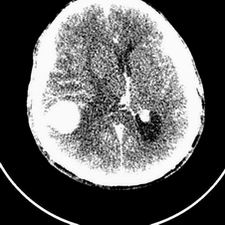

标题: CT25808:男,48岁,头痛多年,近段时间头痛加重伴步态不稳 [打印本页]

标题: CT25808:男,48岁,头痛多年,近段时间头痛加重伴步态不稳

平扫:右颞顶叶病灶呈等低密度伴大面积水肿,脑室受压变形。增强:病灶显著强化。考虑淋巴瘤或黑色素瘤。

1)不排除黑色素瘤可能;建议行mri检查。2)大脑镰下疝。3)脑积水(梗阻性)。